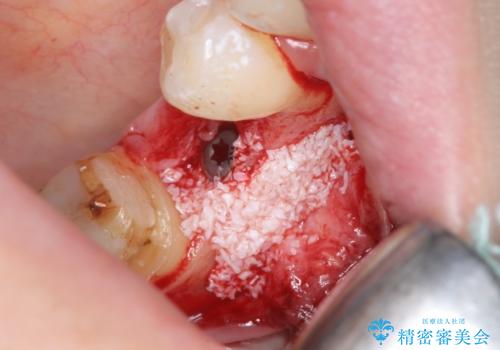

右下7は欠損しており、右下5は保存不可能だったため、インプラントによる欠損補綴を行いました。

インプラント埋入時には骨が不十分な部位に骨増生を行っております。